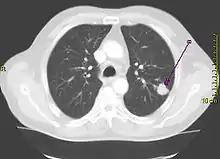

| A chest X-ray showing a tumor in the lung (marked by arrow) | |

A person suspected of having lung cancer will have imaging tests done to evaluate the presence, extent, and location of tumors. First, many primary care providers perform a chest X-ray to look for a mass inside the lung.[8] The X-ray may reveal an obvious mass, the widening of the mediastinum (suggestive of spread to lymph nodes there), atelectasis (lung collapse), consolidation (pneumonia), or pleural effusion;[9] however, some lung tumors are not visible by X-ray.[5] Next, many undergo computed tomography (CT) scanning, which can reveal the sizes and locations of tumors.[8][10]

Lung cancer can often appear as a solitary pulmonary nodule on a chest radiograph or CT scan. In lung cancer screening studies as many as 30% of those screened have a lung nodule, the majority of which turn out to be benign.[15] Besides lung cancer many other diseases can also give this appearance, including hamartomas, and infectious granulomas caused by tuberculosis, histoplasmosis, or coccidioidomycosis.[16]